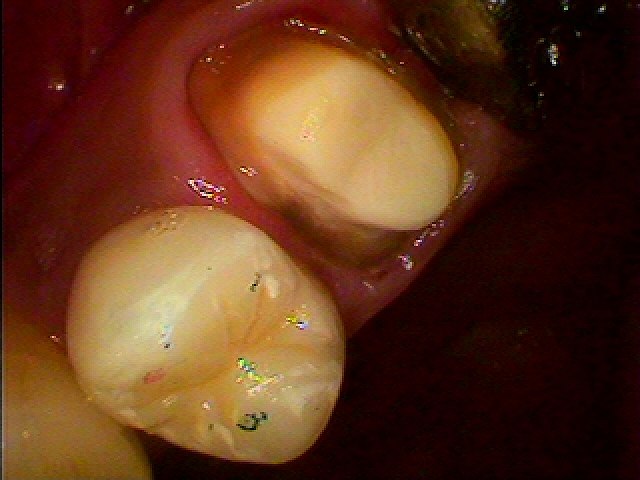

5番はこのようにセラミッククラウンが入っています

咬合面の裂溝にステイニングしてあります。

銀歯と違い歯らしくきれいなセラミッククラウンが入りました

口蓋側から見てもきれいに仕上がっています

頬側からもしっかりと歯肉内にセラミックの立ち上がりが入っています